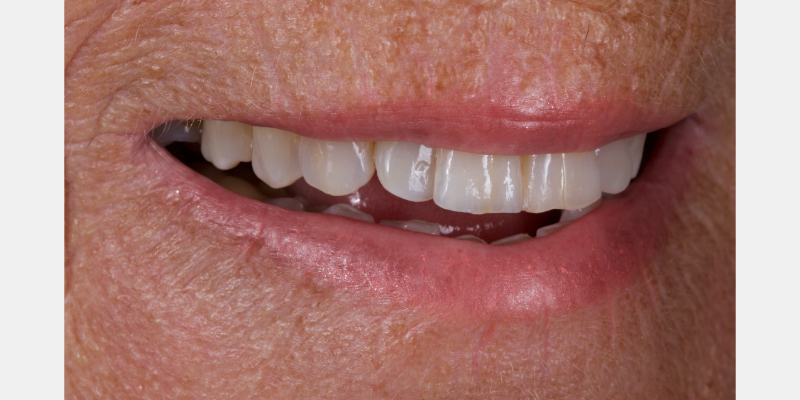

Take Arthur, a 76-year-old man who presented with a vertical root fracture of his upper left central incisor. His medical conditions precluded his request for an implant, so he agreed to the proposal for an adhesive bridge instead.

The tooth was extracted and for four months the pontic site was conditioned with a removable Essix-type of denture (Fig. 1).

An e.max (lithium disilicate), one-wing (adjacent central being the retainer) bridge was placed, which resulted in an acceptable outcome (Figs. 2-4) that was more timely and at a lower financial and biological cost to the patient than the implant Arthur initially thought he wanted.